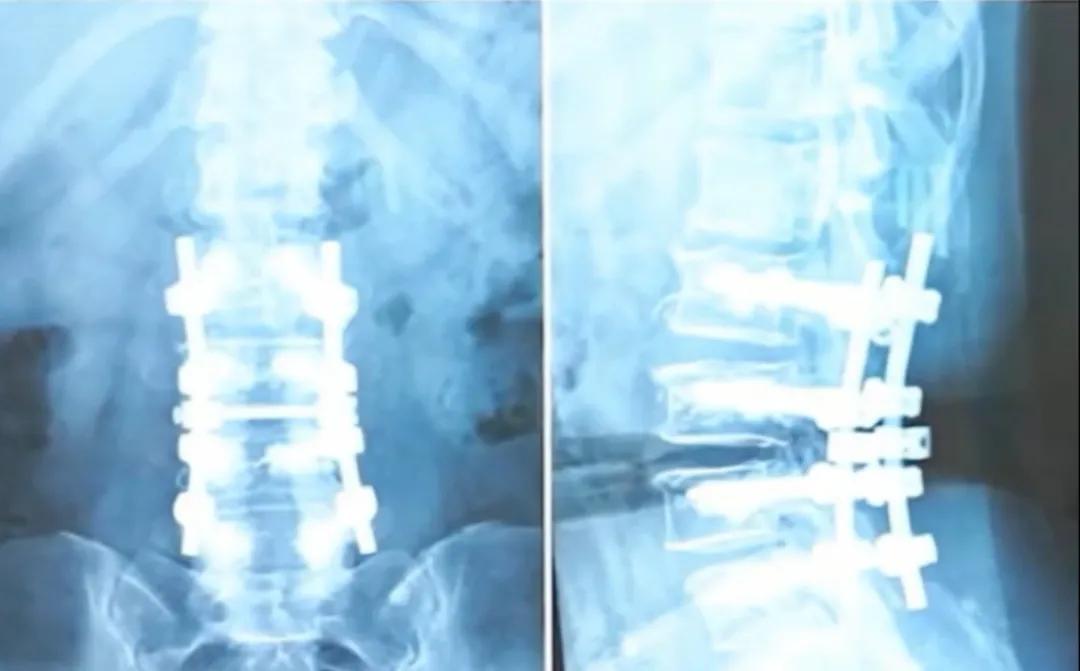

Wie in dem Video gezeigt, konnte eine über 50-jährige Patientin, die wegen schwerer Spinalkanalstenose und Osteoporose operiert wurde, trotz der Implantation von vier Paar (insgesamt acht) Schrauben und der Verwendung von Knochenzement zur Stabilisierung ihrer Wirbelsäule, nach der Operation immer noch sehr flexibel sein und sogar mit beiden Händen den Boden berühren.